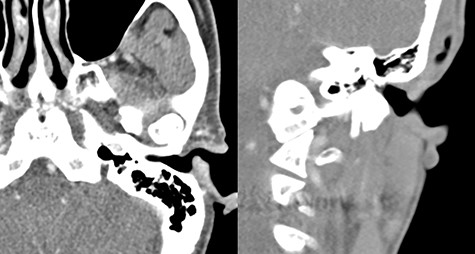

A 54-year-old woman visited our otorhinolaryngology clinic for a cystic mass in the left EAC with intermittent bleeding for several years. On physical examination, a 0.6 × 0.6 cm, soft, pinkish, cystic mass was observed in the posterior cartilaginous portion of the left EAC (Fig. 1). Facial computed tomography (CT) revealed an enhanced cystic mass in the posterior cartilaginous portion of the left EAC (Fig. 2). Considering a vascular tumor, surgical excision was planned because the patient had intermittent symptoms of bleeding.

Facial CT revealing an enhanced cystic mass in the posterior cartilaginous portion of the left external auditory canal. (A) Axial view and (B) coronal view.